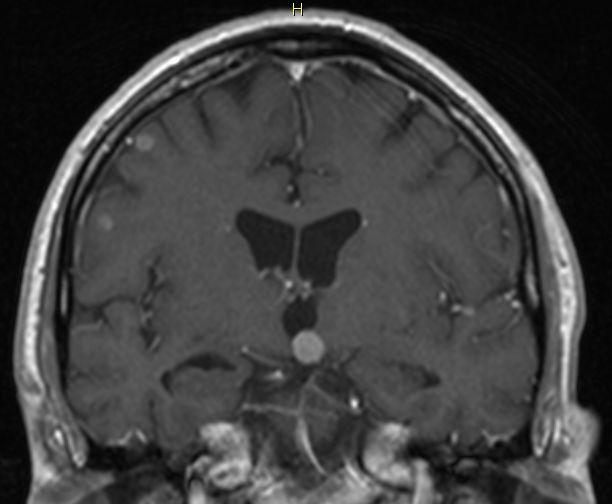

MRT: multiple Hirnmetastasen

70-jähriger Mann, der vor einem Jahr ein Adenokarzinom des rechten Lungenmittellappens hatte. MRT-Untersuchung des Hirns, T1-Sequenz mit Kontrastmittel. Klinisch keine Symptome!